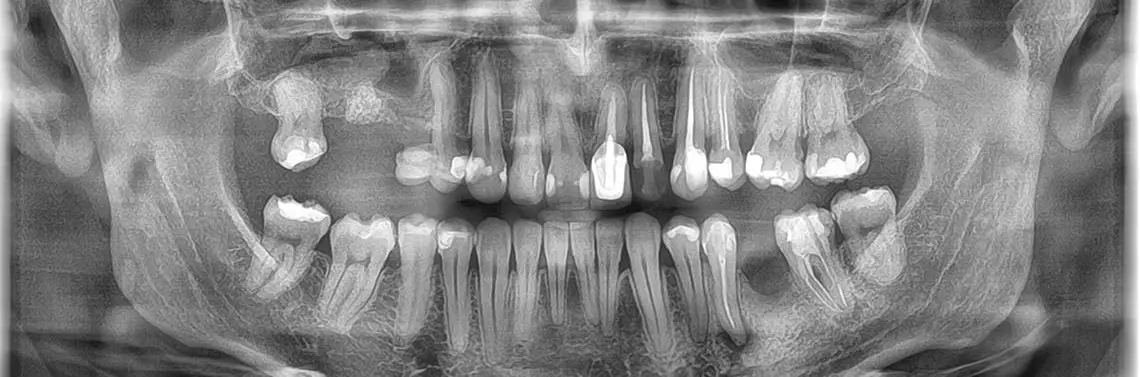

Przypadek 1. – Ryan Walsh DDS, Keller Texas, USA

71-letnia pacjentka została przyjęta w gabinecie. Uskarżała się na obrzęk dziąseł w pobliżu mostu, który był sporadycznie bolesny. Zgłosiła również łagodny dyskomfort podczas żucia. Pacjentka miała most, który istniał od 20 lat. Wstępne badanie wykazało pionowy ubytek kostny wzdłuż mezjalnej powierzchni korzenia na poziomie grzebienia kostnego i widoczną dużą zmianę okołowierzchołkową w kształcie litery J na dystalnej powierzchni korzenia drugiego przedtrzonowca żuchwy po lewej str...